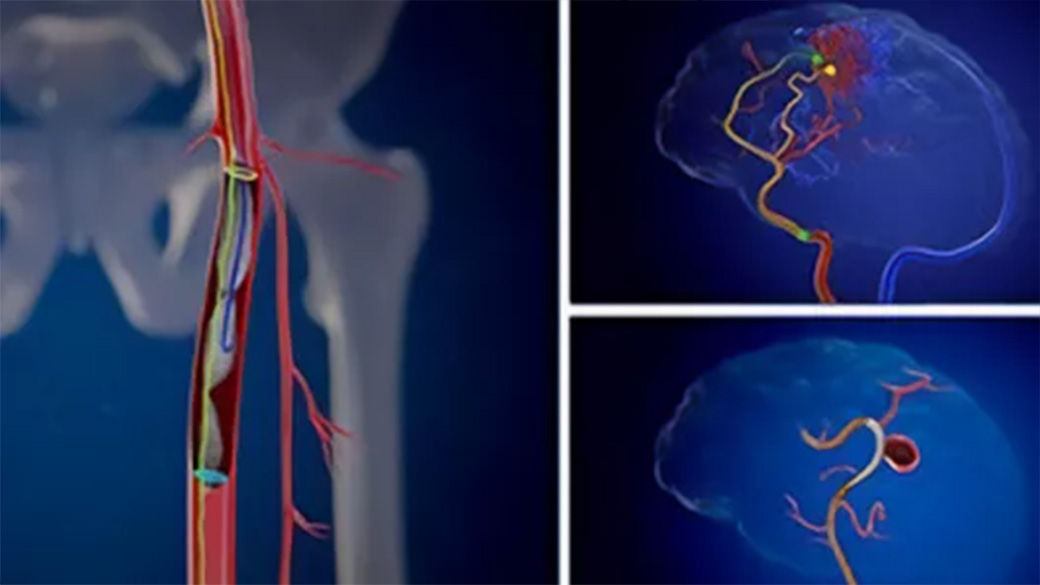

Vessel assist for neurointerventional

Vessel ASSIST delivers accurate and easy anatomy segmentation and accurate vessel quantification from 3D volumes. It also offers advanced 3D roadmap and augmented image guidance capabilities on frontal or lateral planes to guide catheter with confidence for procedure such as Aneurysm Treatment with Flow Diverter.

Plan

Segment and size the anatomy of interest in CBCT.1 Plan the stent positioning on the 3D model and prepare 3D landmarks to help guide the deployment.

Guide

Import segmented anatomy, centerline and landmarks and overlay them on live fluoroscopy on the frontal or lateral plane for 3D fusion guidance.